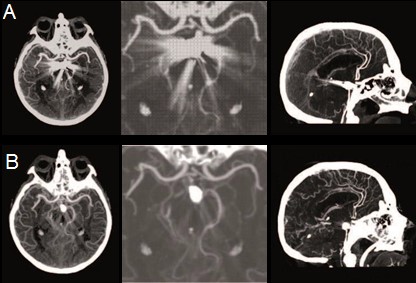

Ở hình 3, bệnh nhân sau can thiệp đặt coil Hubet6677 phiên bản mới túi phình mạch ở đỉnh ĐM thân nền. Chụp CLVT mạch máu não thường quy thấy nhiều nhiễu ảnh do coil (hình A). Hình ảnh tái tạo (Reconstruction) của CLVT phổ với tính năng giảm nhiễu ảnh do kim loại (Metal Artifact Reduction – MAR) sẽ giảm những nhiễu ảnh này, cho phép đánh giá tốt hơn các mạch máu lân cận (hình B).

Hình 3. Hình ảnh chụp CLVT mạch máu não sau đặt coil

A:Hình ảnh không sử dụng MAR ; B: Hình ảnh có sử dụng MAR